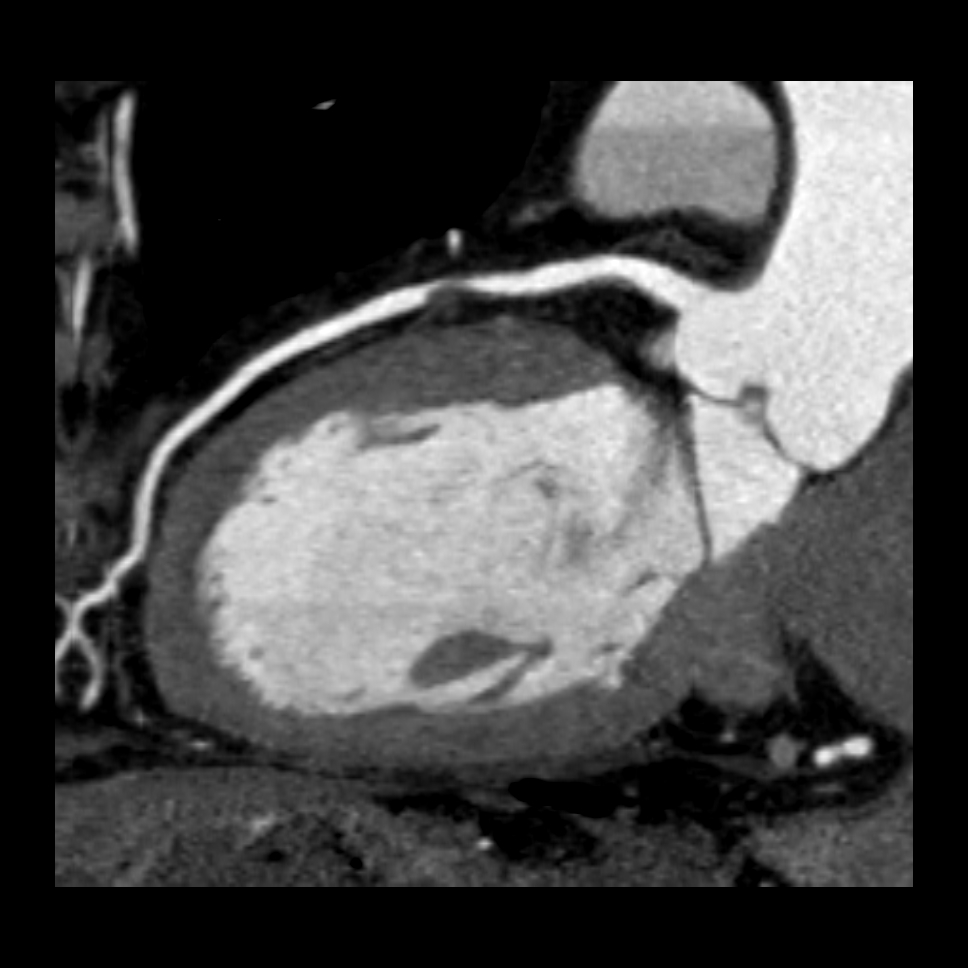

Sie hat sich als eine bedeutende Methode zur nichtinvasiven, das heisst unblutigen Darstellung der Herzkranzgefäße etabliert. Mit Hilfe der CT können bei angemessen ausgewählten und vorbereiteten Patienten mit grosser Zuverlässigkeit Aussagen über das Vorhandensein möglicher Engstellen oder Verschlüsse der Herzkranzgefässe (Abbildung 1), das Ausmass der Herzkranzgefässverkalkungen und die Anatomie des Herzens getroffen werden, und das ohne Herzkatheteruntersuchung. Sind die Herzkranzgefässe bereits erkrankt, so kann unter bestimmten Bedingungen auch eine Darstellung von Bypassgefässen (Abbildung 2) oder Stents erfolgen. Eine blutige Untersuchung mittels Herzkatheter kann somit in vielen Fällen vermieden werden (Abbildung 3). Sollten in der CT relevante Engstellen in einem oder mehreren Koronargefäßen auffallen, muss jedoch meist eine Herzkatheteruntersuchung zur weiterführenden Diagnostik und ggf. Therapie erfolgen.

Abbildung 1: CT – Schnittbild (rechts) sowie dreidimensionale Rekonstruktion (links) zeigen eine hochgradige Engstelle im Bereich der linken Herzkranzarterie.